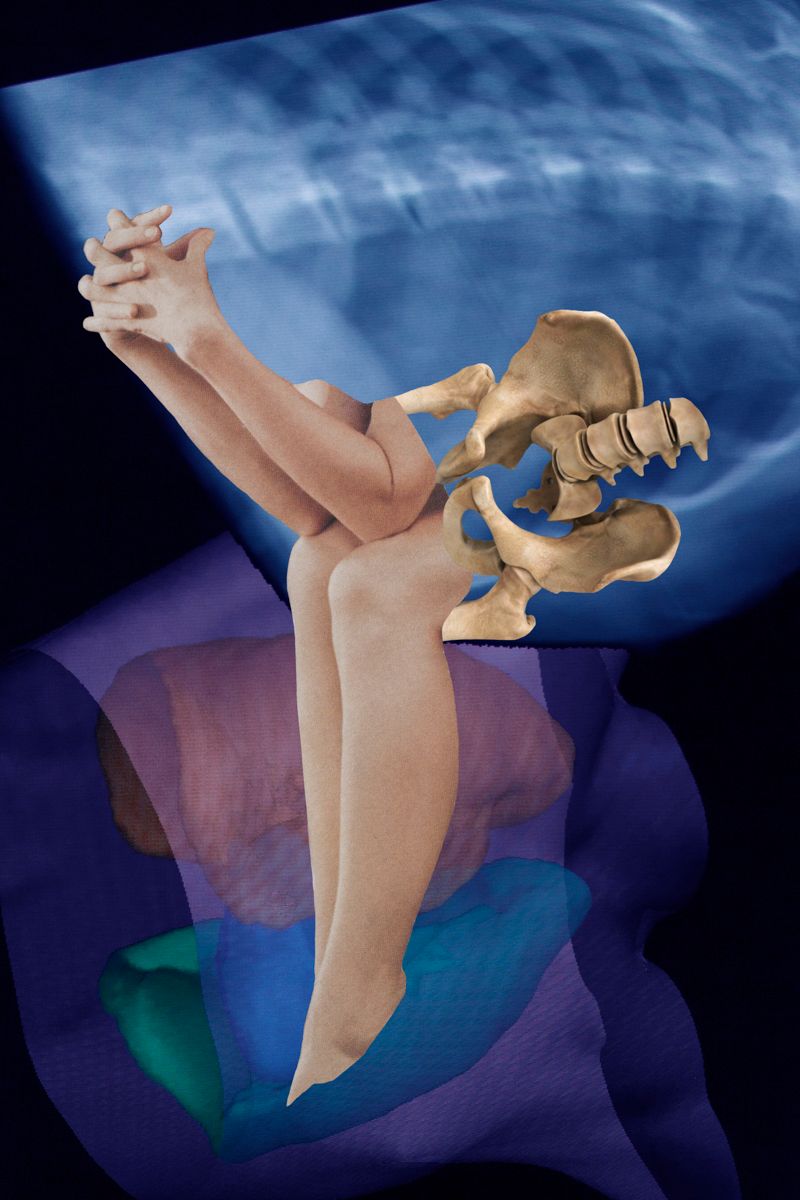

Due to health problems within my family including myself this work derives from a long- term engagement with the human body, its mal-functions and collateral mental issues.

Due to health problems within my family including myself this work derives from a long- term engagement with the human body, its mal-functions and collateral mental issues.

Since the topic being serious and threatening at times, the analysis within the terms of art began to shift from depressing states and strong depictions to more symbolic style of expression alleviating the whole issue.

Combining digital 3-D models of inner organs from the web with scanned cut-outs from magazines, different kind of free associations are made possible. The background consisting of CTs from my check-up enhances the issue of the fragility of our body.

Each image describes a mental state during this period of endurance.